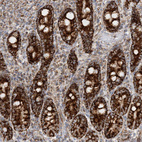

Immunohistochemical staining of human kidney shows strong granular cytoplasmic positivity in cells in tubules.